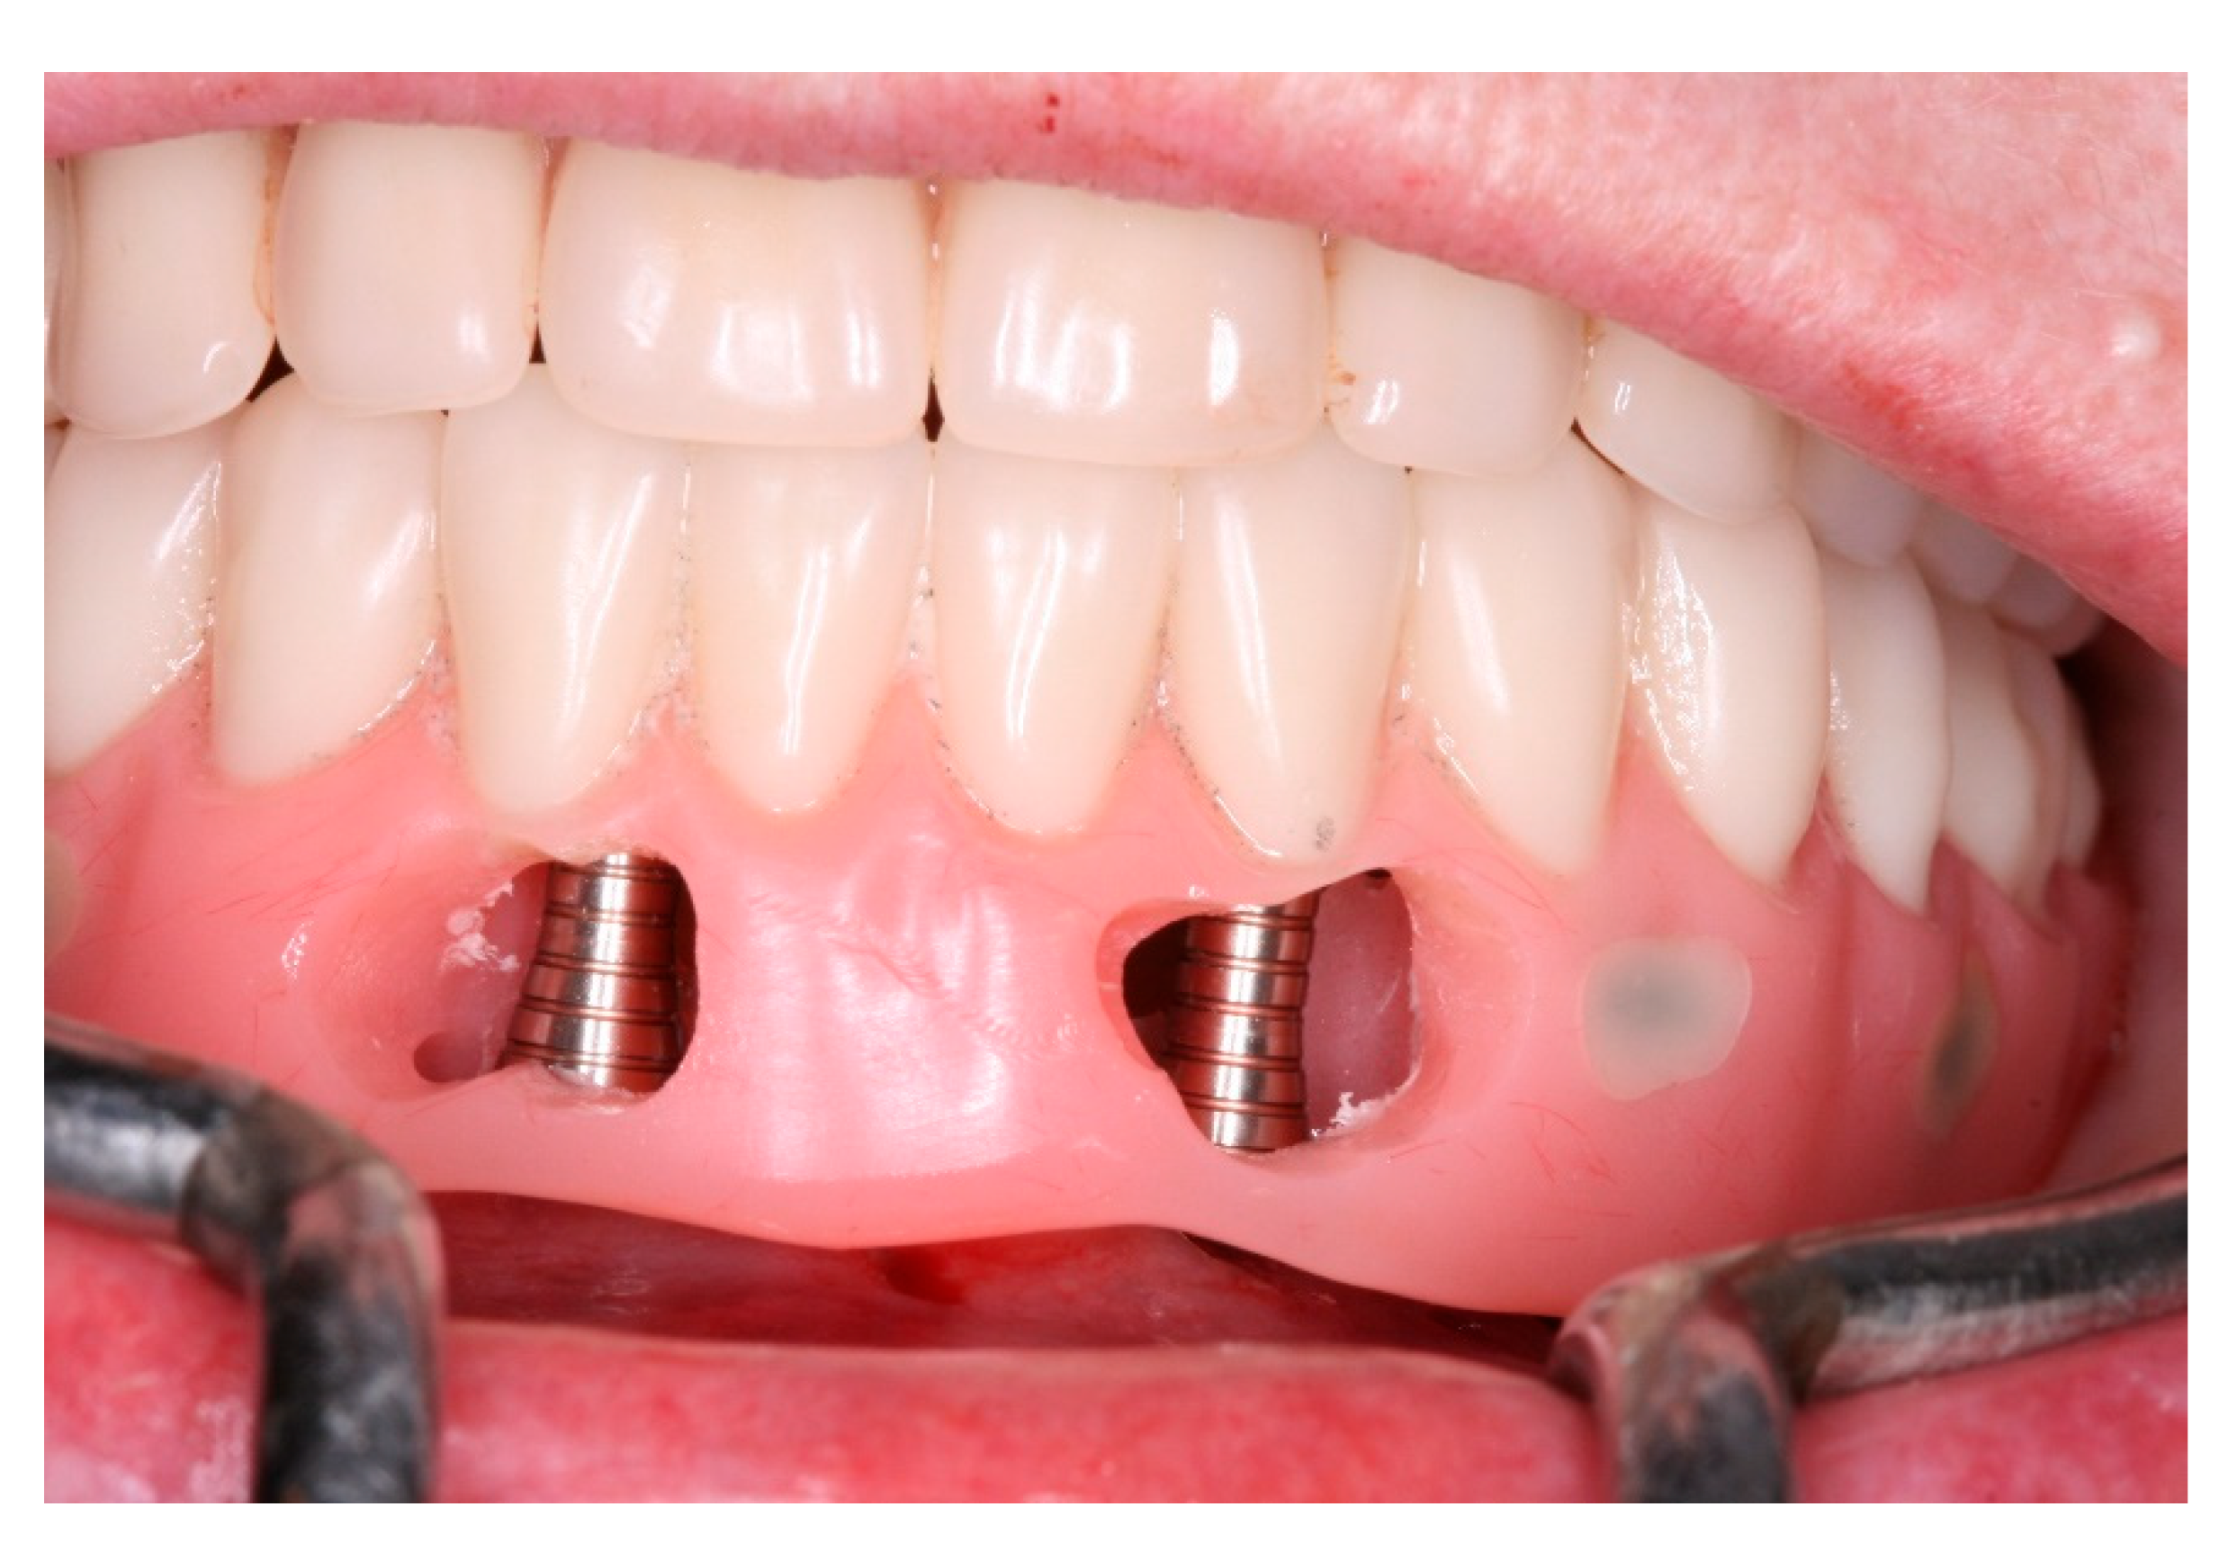

Pre-operatory medication consisted only on 2g of Amoxicillin one hour before the procedure, as suggested by her cardiologist. On surgery day, after anesthesia with Articaine 4% 1: 100,000 (DFL, Rio de Janeiro, Brazil), the computed surgical guide was placed in position, assured by the oclusal position on both sides and the stability over the patient’s mucosa, and in this position, fixed with the fixation pins after using their drills, assuring the guide immobilization (Figure 7). After that, we followed the guided bone instrumentation protocol recommended by the Plenum implant system (Plenum® Bioengenharia- Jundiaí, Brazil) to place 4 dental implants of 4.0x10mm with morse-tapper connection, produced by addtive manufacturing technology using titanium powder grade 23 (Figure 8), without raising a flap (Figure 9 and Figure 10). Because of this detail, very little bleeding was noted during the surgery. All implants were inserted with insertion torque ranging from 45 to 60 N/cm, assuring us the possibility for immediate load. The guide was removed (Figure 11) and four mini-conic abutments (Plenum® Bioengenharia- Jundiaí, Brazil), with 2mm high were installed on the implants. No suture was necessary and minimum trauma was noted on the soft tissue (Figure 12). Over these abutments, titanium cylinders were installed (Figure 13) and the lower denture was prepared to capture the implants position, translating the removable prosthesis into a fixed one (Figure 14 and Figure 15). Pattern Resin was used to unite the denture to the cylinders, and over the red resin, pink acrylic resin was used to improve the aesthetic appearance of the prosthesis. The denture was worn out in order not to touch the patient’s mucosa, and to diminish the cantilever we removed the molars from both sides of the denture (Figure 16) and installed the temporary fixed screw retained full-arch rehabilitation (Figure 17 and Figure 18). With this, the patient left the surgical appointment with an immediate load implant rehabilitation. Post operatory medication consisted on 600mg of Ibuprofen, twice a day during 3 days, if necessary. She was instructed to put ice bags on the surgical area during 48 hours, about 15 minutes every hour. On the day before surgery the patient suspended the medication because she had no pain. The patient was also instructed not to sleep with the opposing complete denture for 7 days and feed only with soft foods.

Figure 13. View of the titanium cylinders screwed to the abutments.